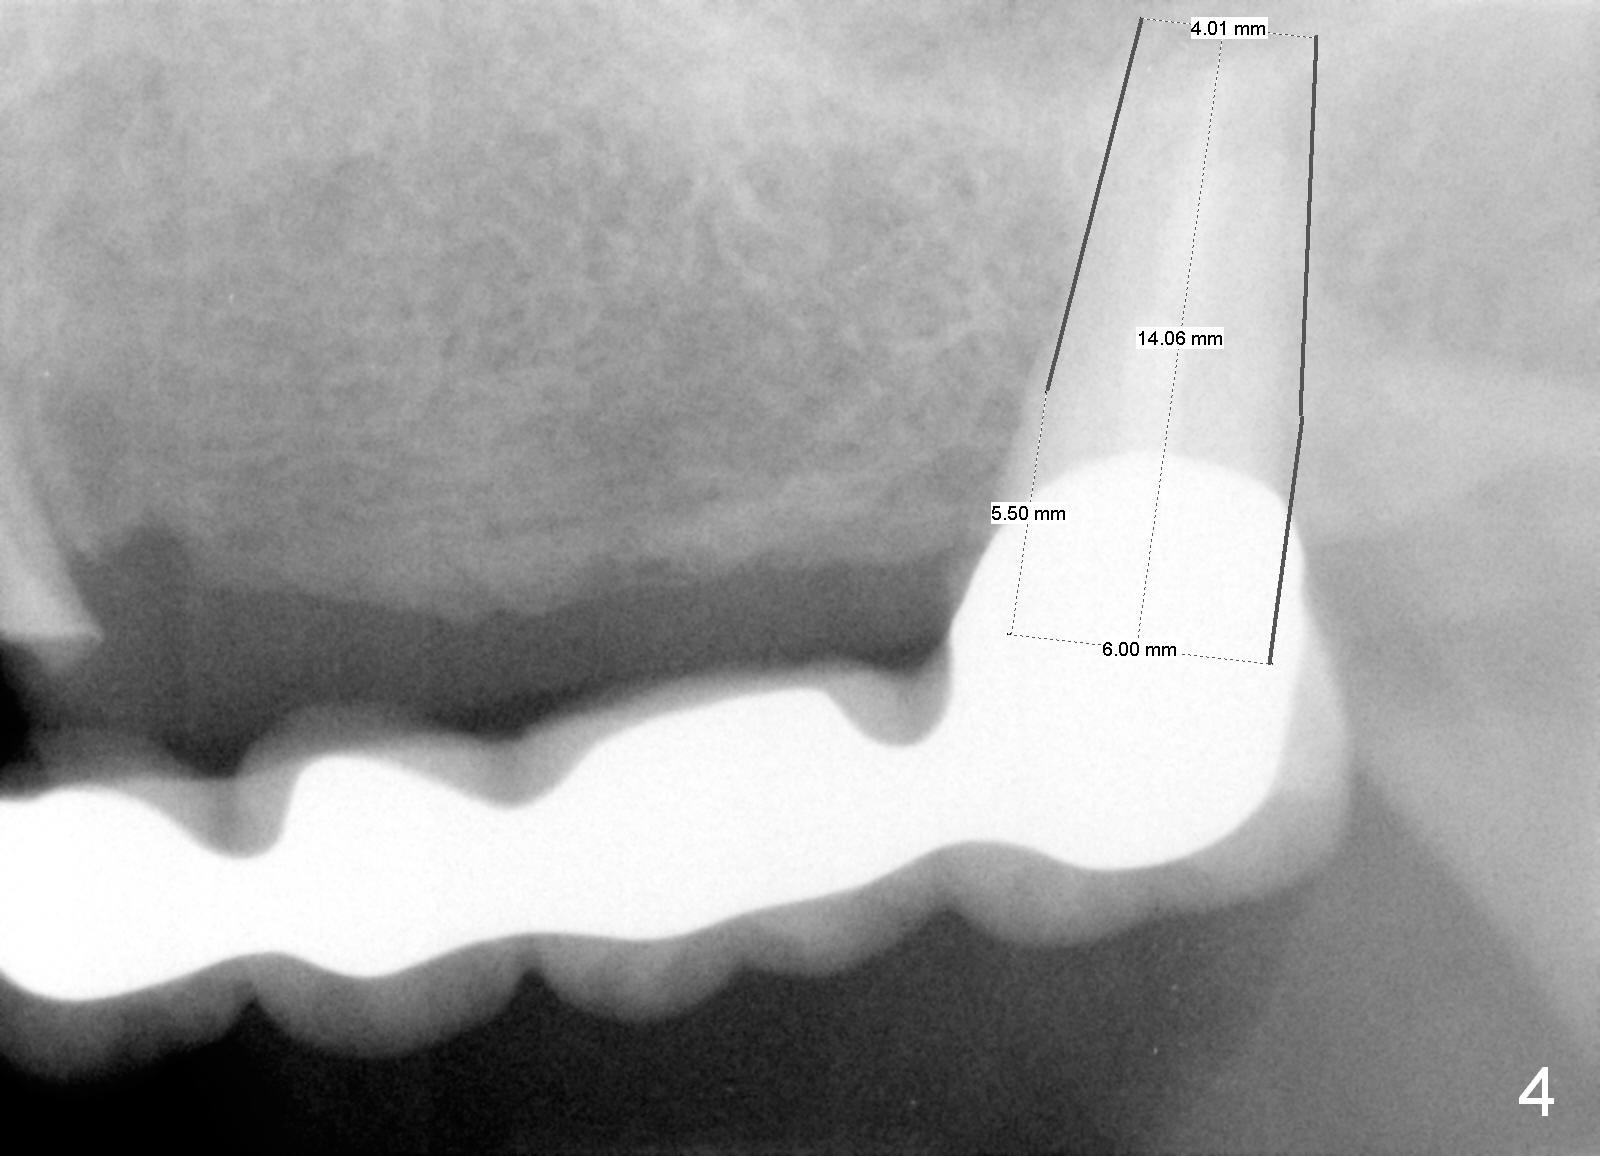

A 68-year-old female has had a long spanned FPD (fixed partial denture, bridge) for the last 2 years. It is loose (Fig.1,2). The patient is concerned about cosmetics, but has limited finance. The FPD dislodges when Alginate impression is being taken. The teeth #11 and 15 will be extracted and replaced immediately by implants (Fig.3,4). After placement of abutments, a 5-unit immediate provisional FPD will be fabricated if the implants achieve primary stability. Otherwise, an additional implant will be placed at the site of #13. There will be no occlusal contact.